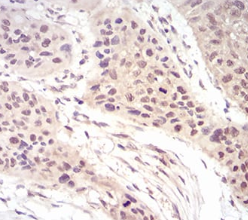

EIF5A Mouse Monoclonal antibody[4E1G8]

IHC    1/200 - 1/1000